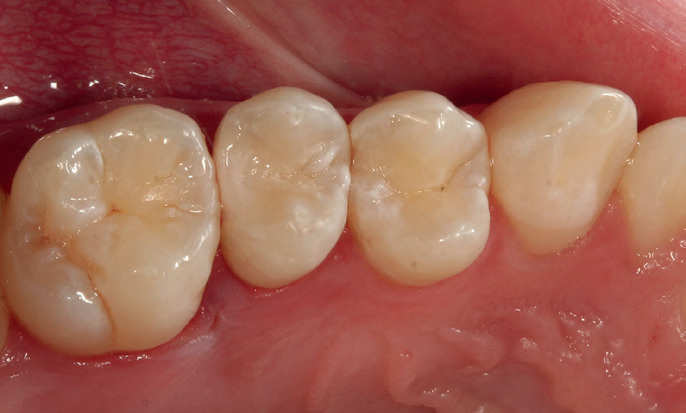

Figure 10: Postoperative images after occlusal adjustment. Two fillings placed UR4 and UR5